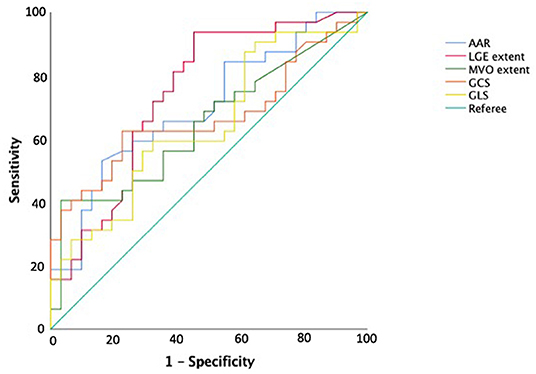

At ROC curve analysis (Figure 3), AAR, IS, MVO, GLS, and GCS values, measured at baseline CMR, showed significant sensitivity (Se) and specificity (Sp) to detect adverse remodeling at FU-CMR (AAR AUC 0.684, 95% CI 0.563–0.789, p = 0.0040 Youden index J 0.3476 with Se: 51% and Sp: 83%; LGE AUC 0.747, 95% CI 0.635–0.859, p < 0.001 Youden index J for LGE > 9.7% with Se: 93% and Sp: 40%; MVO AUC 0.637, 95% CI 0.514–0.747, p = 0.0405 Youden index J for MVO 0.39 gr with a Se: 42% and Sp: 97%; GLS AUC 0.639, 95% CI 0.521–0.745, p = 0.0306 Youden index J > −10.21 % with Se: 35% and Sp: 90%; GCS AUC 0.660 95% CI 0.543–0.764, p = 0.0138 Youden index J > −11.09 % with Se: 43% and Sp: 92%). In pairwise comparisons, there were no significant differences between the AUC of ROC curves of the measured CMR parameters by DeLong et al. (20) method (p > 0.05 for all). About infarct related artery, significantly worse GCS and GLS were observed in those having, as the culprit lesion, the left anterior descending artery (LAD) compared to circumphlex (LCX) and right coronary arteries (RCA) (GCS values in LAD −13.0 ± 4 vs. −16.0 ± 3% in LCX vs. −15.1±3% in RCA, p = 0.014; GLS values −12 ± 4% in LAD vs. −16.1 ± 3% in LCX vs. −15.4 ± 2% in RCA, p < 0.001).

Figure 3. Receiver operating curve analysis for predicting adverse left ventricular remodeling. AAR, area-at-risk; LGE, late gadolinium enhancement; MVO, microvascular obstruction; GRS, global radial strain; GCS, global circumferential strain; GLS, global longitudinal strain.

In this study, we categorized the population using the three LV remodeling patterns based on Bulluck's definition (7), observing a similar percentage distribution (adverse remodeling 49 vs. 45%, reverse remodeling 28 vs. 29%, and null remodeling 19 vs. 23%). For CMR parameters, the adverse remodeling group showed greater AAR, IS, and MVO at baseline CMR and greater IS at FU-CMR, as already reported (7). Otherwise, no differences in IS and MVO between reverse and null remodeling groups were found in our study. Notably, there were no differences in salvage myocardium extent among the three groups. Although IS and MVO are known predictors of adverse remodeling (7), the relationship between them and myocardial recovery is still an open issue (6, 7). Moreover, at FU-CMR, the adverse remodeling group showed lower LVEF, LV-RI, and greater IS, as compared to the other two groups. Regarding FT-CMR strain analysis, the adverse remodeling group showed worse GCS and GLS values at baseline and FU-CMR (Figure 5), if compared to reverse and null remodeling categories as one. Various studies investigated the value of FT-CMR features in predicting adverse remodeling (11, 12, 22), using different cut-off values and follow-up periods. For the definition of adverse LV remodeling, we considered LVEDV and/or an LVESV delta change of 12%, which is lower than most reports, and 6 months for follow-up, longer if compared to other studies, mostly around 3/4 months. Thus, this issue may have induced a larger rate of adverse remodeling in our population (49%), as compared to other cohorts (17–24.4%) (11, 12, 22, 23). In the majority of studies, baseline GLS was the best predictor of adverse remodeling among all strain values (11, 22–24). In particular, Reindl et al. (22) reported significant differences in baseline strain values and infarct size/MVO percentage between no remodeling and remodeling groups, as observed in our cohort. Moreover, they showed that a GLS-value > −14% was the best independent predictor of 4 months LV adverse remodeling (LVEDV delta change of 10%) with an AUC of 0.610, which do not differ substantially from our GLS AUC value of 0.639 using LVEDV/LVESV delta change of 12%. In the retrospective study of Cha et al. (11), at ROC curve analysis (AUC: 0.756, 95% CI = 0.636–0.887, p < 0.001), the GLS cut-off of −12.84% resulted in high sensitivity (Se: 85%) and low specificity (Sp: 61%) in predicting adverse remodeling at 6 months (LVEDV delta change of 20%), whereas in our study the optimal cut-off was lower (GLS > −10.21%), with lower sensitivity (Se: 35%) and higher specificity (Sp: 90%), likely reflecting the different criteria in classifying the remodeling groups. Interestingly, in our study GCS was the strongest predictor of adverse remodeling among the baseline strain values, as already reported by other authors (12, 25, 26). Holmes et al. (12) found that GCS was a superior predictor of LV adverse remodeling at 3 months follow-up than MVO, GLS, and GRS, although they considered a cohort of both STEMI and non-STEMI patients (12), differently from our population of STEMI only. Similarly, Buss et al. demonstrated that GCS is useful in predicting preserved LV function at 6 months follow-up but they did not evaluate LV remodeling groups (25).

For the other CMR factors, we compared strain parameters and IS in predicting adverse remodeling, demonstrating high sensitivity for IS cut-off of 9.7% (Se: 93%), whereas the GCS and GLS may offer high specificity at the optimal cut-off values (Sp: 92 and 90%, respectively). These results support the evidence that both GCS and GLS values are both useful in the prognostic stratification of STEMI patients and should be interpreted in combination with other CMR parameters, to improve risk profiling and tailoring of therapies.